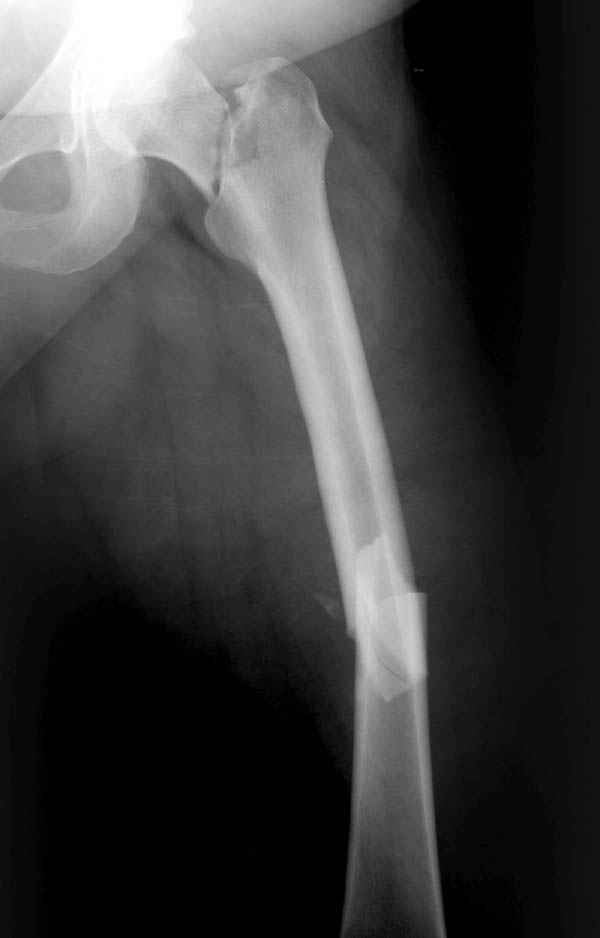

Из-за опасности вторичного смещения переломов "без смещения" во время интрамедуллярных манипуляций, особенно при ретроградном введении, необходимо каждый случай протоколировать с описанием состояния шейки после операции.

Установленный в бедро штифт, без стимуляции, не гарантирует сращение.

А не опорная болтающаяся конечность с большим рычагом усложнит состояние перелома шейки и поэтому ипсилатеральные переломы, тем более ятрогенные, очень часто осложняются двойными ложными суставами.

This is very bad situation. To miss fracture subcapital like this is unforgivable. Now the fracture of the femoral shaft isn't healed with malreduction component and fracture of the subcapital femur (doesn't matter what grade) without any chance for healing. More of them, therк is very high chanse to AVN of the femoral head. At the moment nothing can be done exept change of the intramedullary nail in femoral shaft

with femoral neck fixation after open reduction . I mean PF Aesculap nail or TAN Smith & Nerphuy). After that waiting with hoope to union of the femoral shaft fracture and, depending on condition of the femoral head, in the life - suprise, or go to THR noncemented if the head will be dead. Any way this young man is invalid. Good luck !